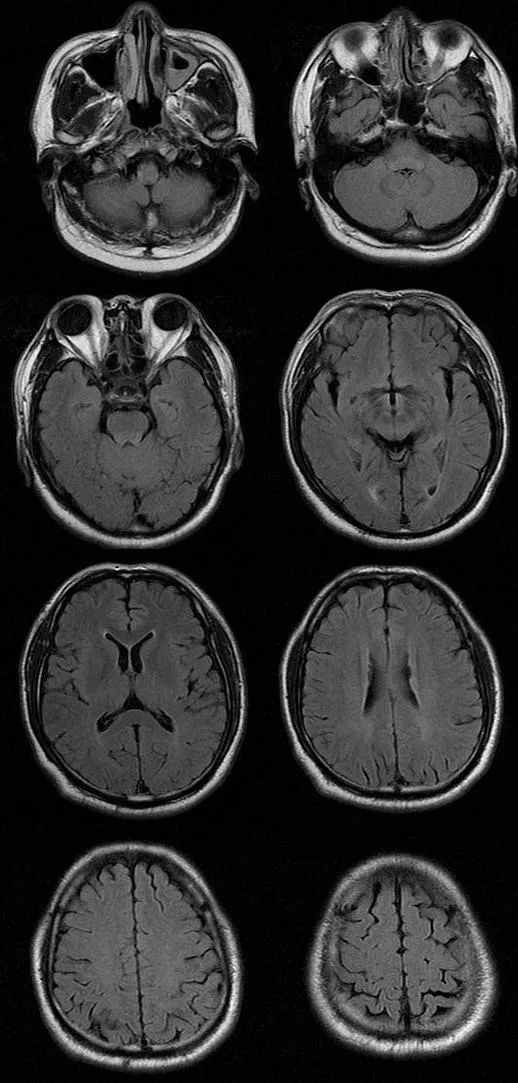

遗憾的是胸腰部 MRI 中 T1、T2、STIR 均未见明显异常,我们进一步完善头部 MRI,如下图:

T2FLAIR

从影像学可以看出 T2FLAIR、T1、T2 似乎也未见明显异常,此时该如何诊断,定位到底在哪里呢?

让我们再仔细看一下 DWI:

DWI 提示右侧延髓背外侧小点状高信号,弥散受限,提示急性脑梗死。